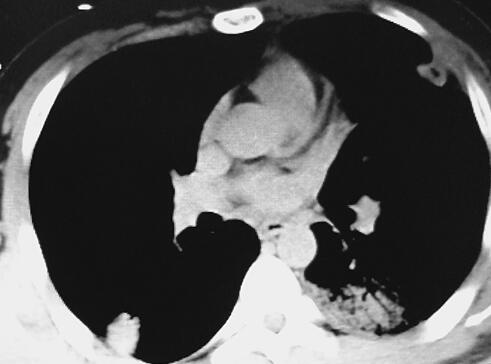

行肺部结节穿刺活检可见纤维素样物和少许淋巴细胞、中性粒细胞浸润。查经胸超声心动图可见左心室腱索赘生物16mm×13mm。诊断“感染性心内膜炎、机化性肺炎”,给予美洛西林+依替米星输液治疗3周,患者病情仍逐渐加重,每日发热体温最高可达41℃。

因感染控制不佳,考虑为心脏瓣膜局部病灶未清除所致。为行心脏手术转至笔者医院。笔者医院复查心脏超声提示赘生物20mm×11mm,体温持续在40℃以上,心率可达160次/分。因患者一般状况迅速变差,转来笔者医院急诊,因病情危重入抢救室。个人史、既往史无特殊。